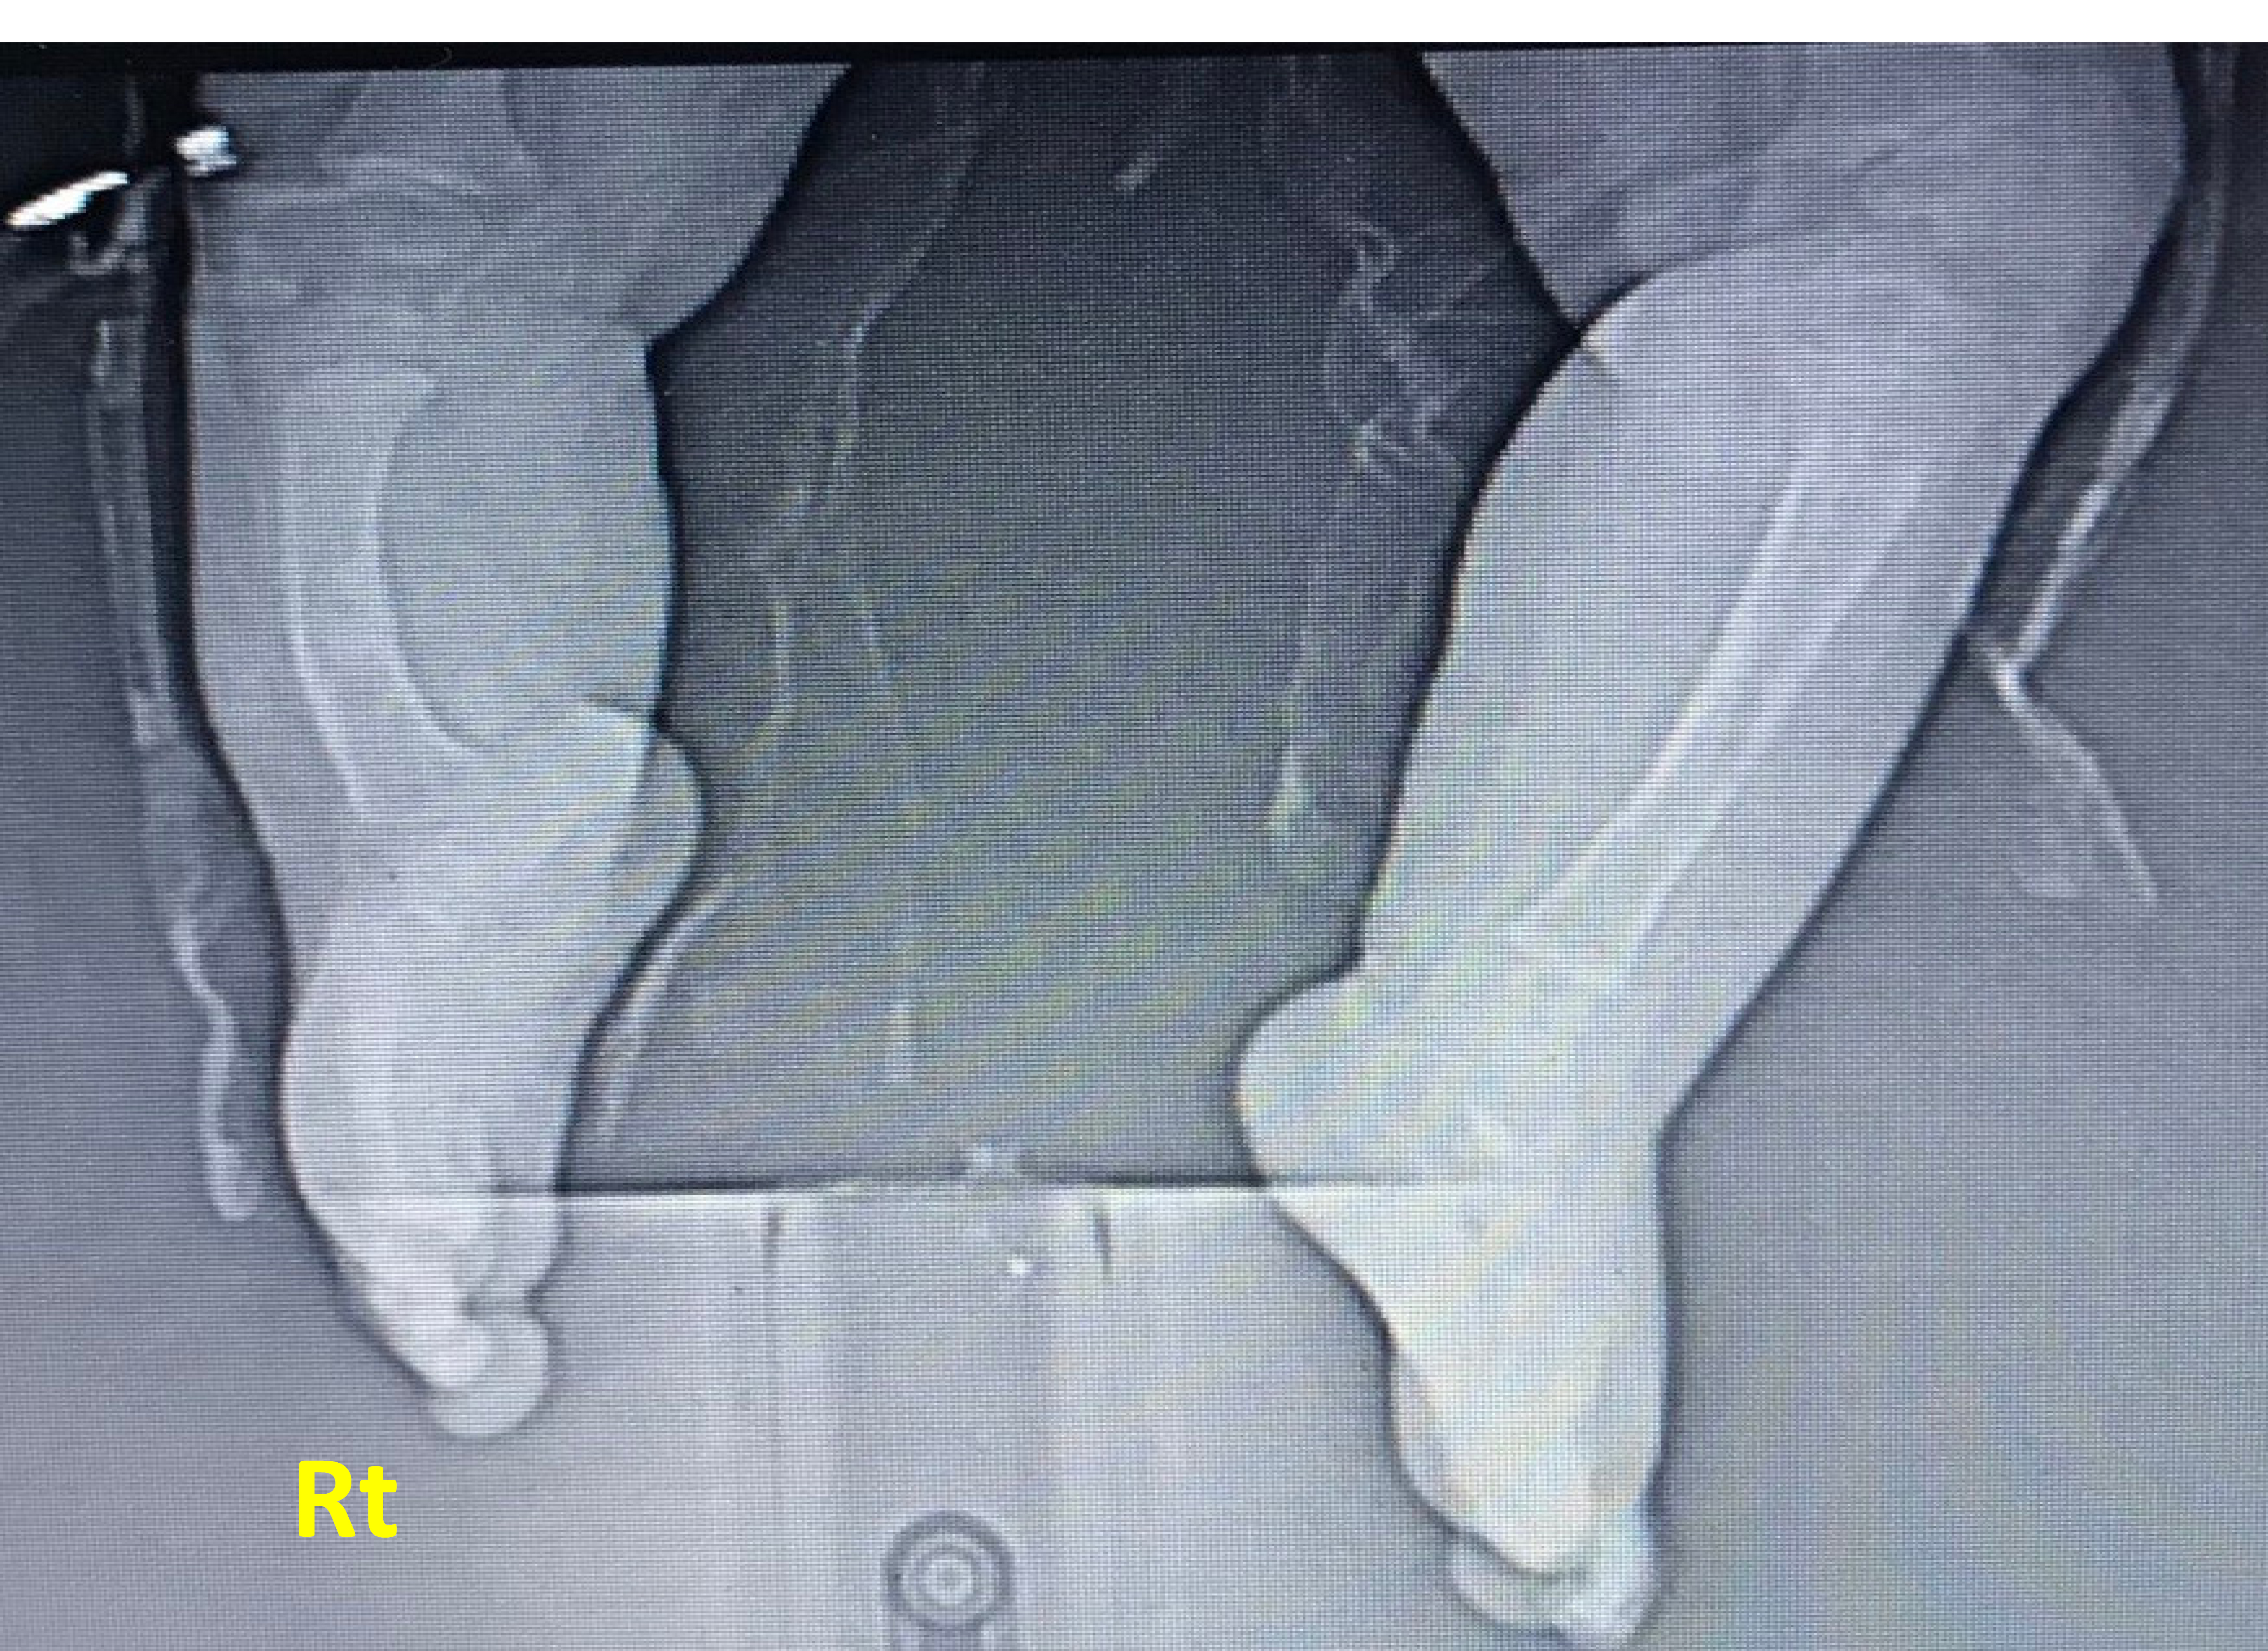

X-ray posteroanterior projection of both Rt and Lt legs; the Rt leg is shortened with thickened bowing of tibial bone, thickened cortex borders, and irregular bony marrow trabeculation compared with the normal Lt leg. Fibula is absent, associated with a hypoplastic, deformed attachment of the distal tibia to the ankle region, and later showing irregular hypoplastic carpal bony fusion.